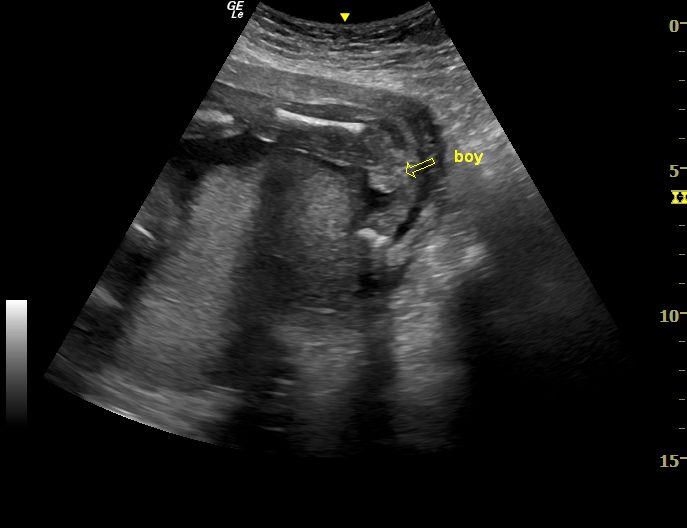

Monday I went for my 20 week ultrasound, at 20w 2d. Though I had swayed girl, I was expecting to hear boy, and did, pointing to this picture and the "good looking scrotum" in it. Well 5 minutes after this, the baby pottied (which was pretty cool to see, actually) and the tech suddenly got a bit flustered and changed his tune. "I apologize," he said, "I think that is a girl. We should have seen a clear penis pop out there when the baby went, and I don't see that. Sometimes the labia gets swollen and makes it hard to tell...I'm like 90/10...never 100%..." and I didn't hear any more and wouldn't have believed a word of it at that point anyway. I assumed he had grabbed a couple of photos for me on my usb drive after his flip flop, but discovered when I got home that he hadn't. So I have no comparison shots. Nothing clear enough either way. Now I am debating what to do. I have to have another ultrasound in 8 weeks due to a low lying placenta, but 1. I don't know if I can wait that long, and 2. I don't really want to pay for an extra ultrasound in between. On the upside, the next one should be done by my regular guy who I have seen in my last 4 pregnancies, and I tend to trust him more.